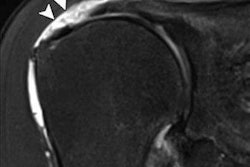

A posterior labral tear (arrow) in a 20-year-old man detected with axial T2-weighted multiplanar 2D fast spin-echo unenhanced standard MRI (above) and the fast five-minute protocol (below) using 3-tesla MRI. Images courtesy of AJR.The key component to reducing imaging time and maintaining diagnostic image quality is having a scanner that can perform parallel imaging. The technology shortens exam time by obtaining a signal from a reduced field-of-view with fewer phase-encoding steps, which allows "images to be acquired with the same resolution as that obtained with a standard sequence in less time," the authors wrote.